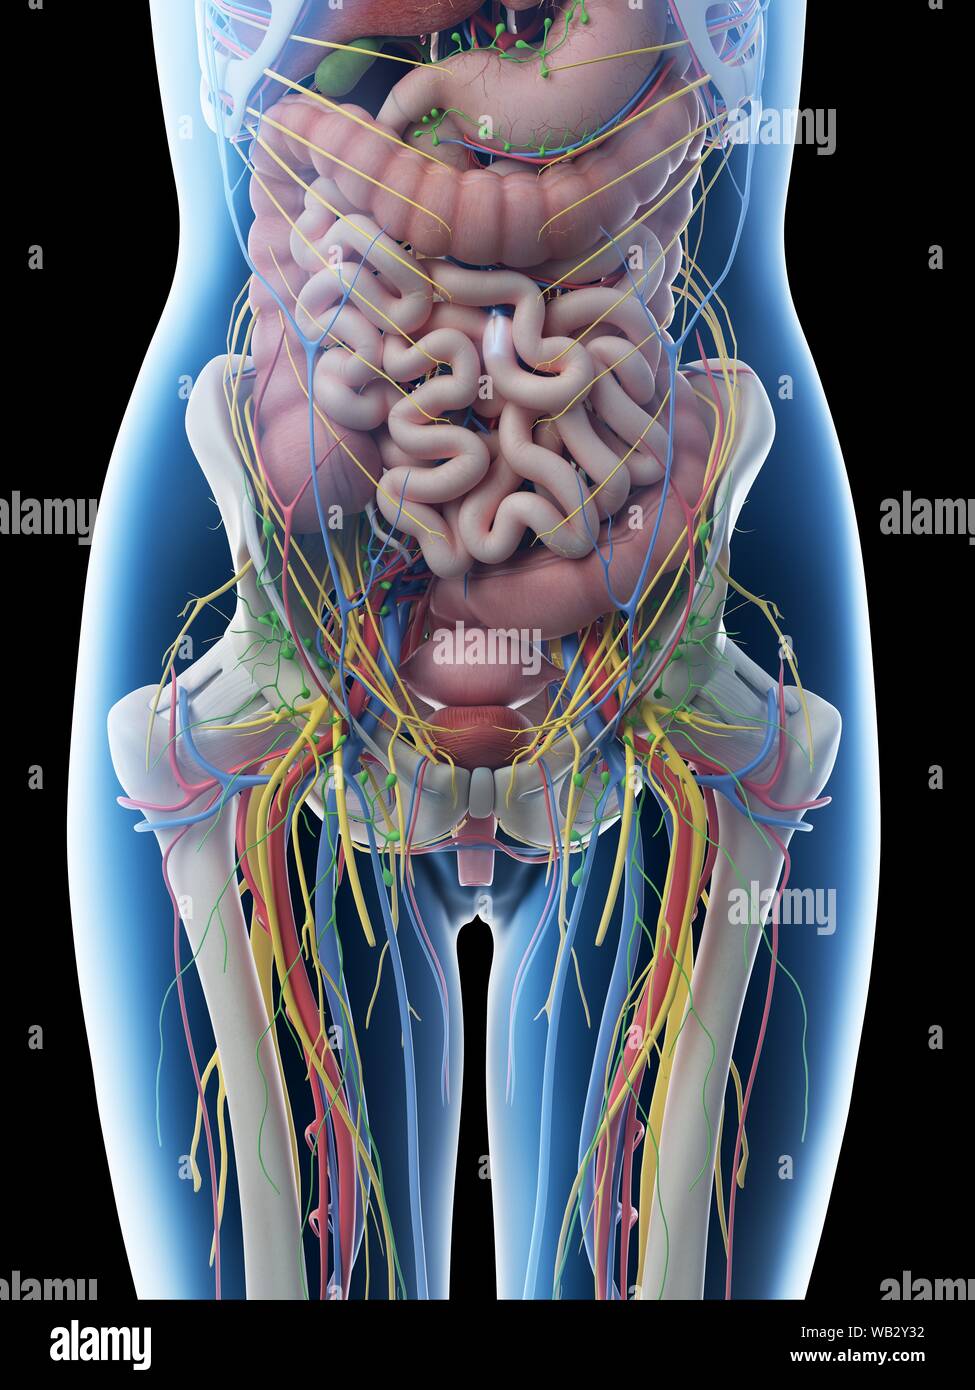

Anatomie de l'abdomen femelle, illustration de l'ordinateur. Banque D'Imageshttps://www.alamyimages.fr/image-license-details/?v=1https://www.alamyimages.fr/anatomie-de-l-abdomen-femelle-illustration-de-l-ordinateur-image264981899.html

Anatomie de l'abdomen femelle, illustration de l'ordinateur. Banque D'Imageshttps://www.alamyimages.fr/image-license-details/?v=1https://www.alamyimages.fr/anatomie-de-l-abdomen-femelle-illustration-de-l-ordinateur-image264981899.htmlRFWB2Y37–Anatomie de l'abdomen femelle, illustration de l'ordinateur.

Anatomie de l'abdomen femelle, illustration de l'ordinateur. Banque D'Imageshttps://www.alamyimages.fr/image-license-details/?v=1https://www.alamyimages.fr/anatomie-de-l-abdomen-femelle-illustration-de-l-ordinateur-image264981886.html

Anatomie de l'abdomen femelle, illustration de l'ordinateur. Banque D'Imageshttps://www.alamyimages.fr/image-license-details/?v=1https://www.alamyimages.fr/anatomie-de-l-abdomen-femelle-illustration-de-l-ordinateur-image264981886.htmlRFWB2Y2P–Anatomie de l'abdomen femelle, illustration de l'ordinateur.

Anatomie de l'abdomen femelle, illustration de l'ordinateur. Banque D'Imageshttps://www.alamyimages.fr/image-license-details/?v=1https://www.alamyimages.fr/anatomie-de-l-abdomen-femelle-illustration-de-l-ordinateur-image264981894.html

Anatomie de l'abdomen femelle, illustration de l'ordinateur. Banque D'Imageshttps://www.alamyimages.fr/image-license-details/?v=1https://www.alamyimages.fr/anatomie-de-l-abdomen-femelle-illustration-de-l-ordinateur-image264981894.htmlRFWB2Y32–Anatomie de l'abdomen femelle, illustration de l'ordinateur.